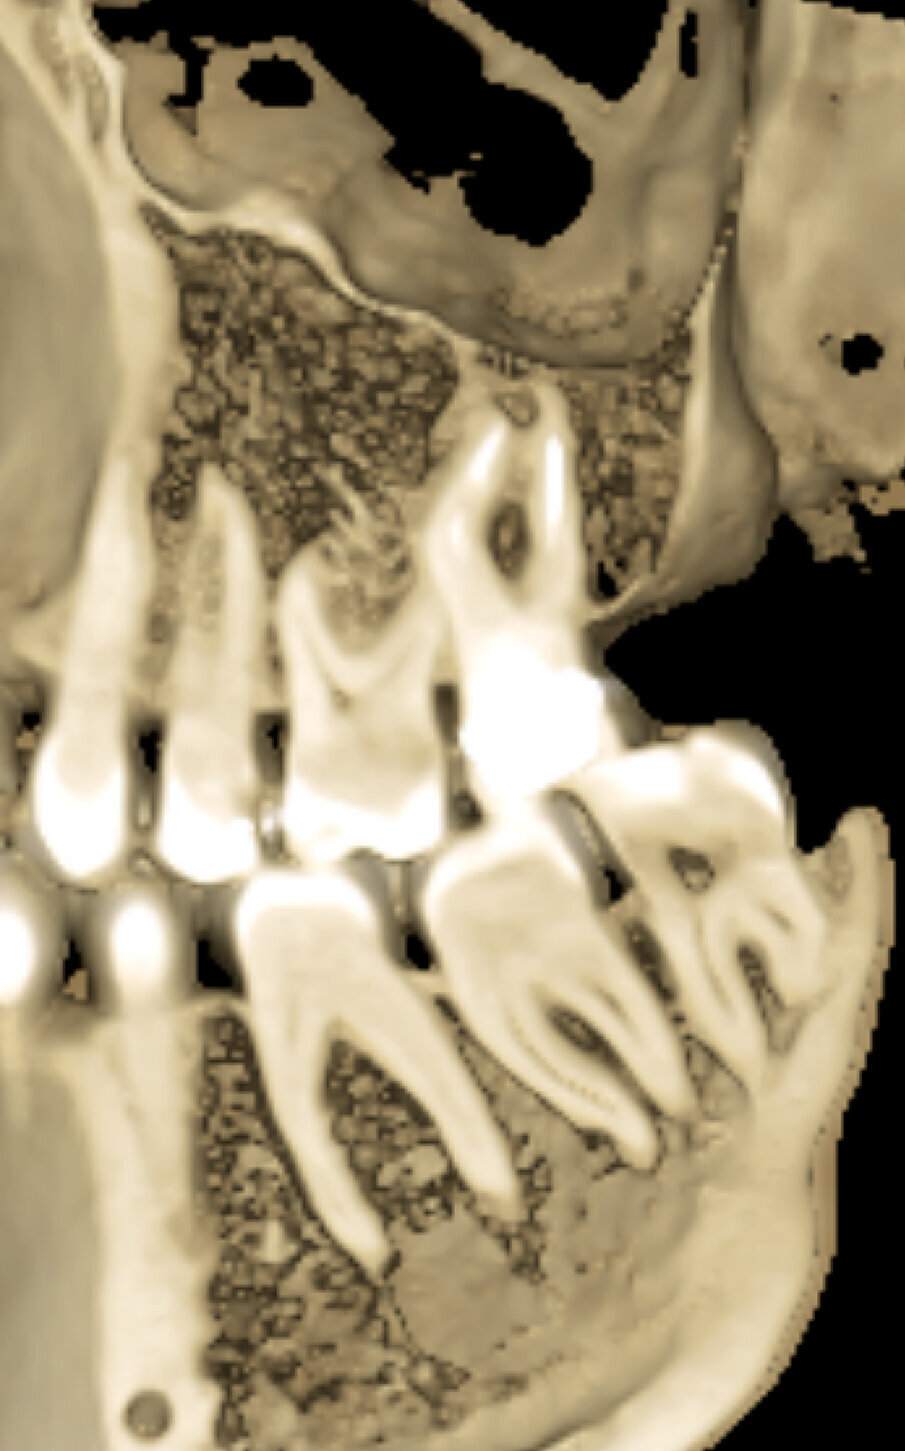

Fig. 1c - La CBCT mostra il riassorbimento dell’osso corticale adiacente la radice distovestibolare.

Figg. 1d, 1e - Un’altra lesione periapicale sta interessando il secondo molare.

Fig. 1f, 1g - La sezione sagittale mostra ancora meglio le lesioni a carico del primo molare su entrambe le radici vestibolari e le lesioni a carico di entrambe le radici vestibolari del secondo molare, il cui canale MB1 appare completamente vuoto.

Fig. 1h - La sezione assiale mostra le lesioni del primo e del secondo molare, interessanti queste ultime per l’aspetto palatino delle due radici. È ovvio il motivo per cui tali lesioni non erano apprezzabili nella radiografia periapicale.